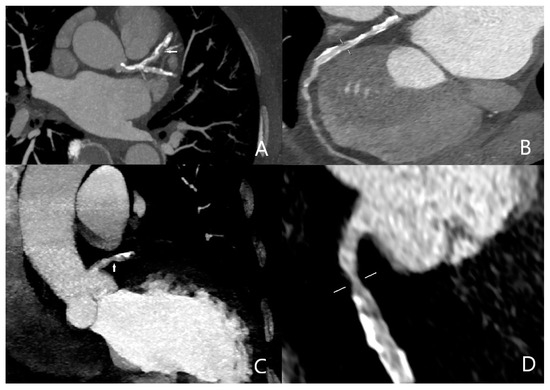

All of the aortic dissection cases were successfully detected with quadruple-rule-out CT angiography protocol (Figure 4). Sensitivity, specificity, and positive and negative predictive value of quadruple-rule-out CT for aortic dissection were 100% (95% CI). Cohen’s coefficient of variation (ĸ value) for the presence of aortic dissection was 1 (perfect).

Figure 4.

Stanford type B aortic dissection affecting both ascending and descending aorta (arrows). ((A) sagittal; (B) coronal).